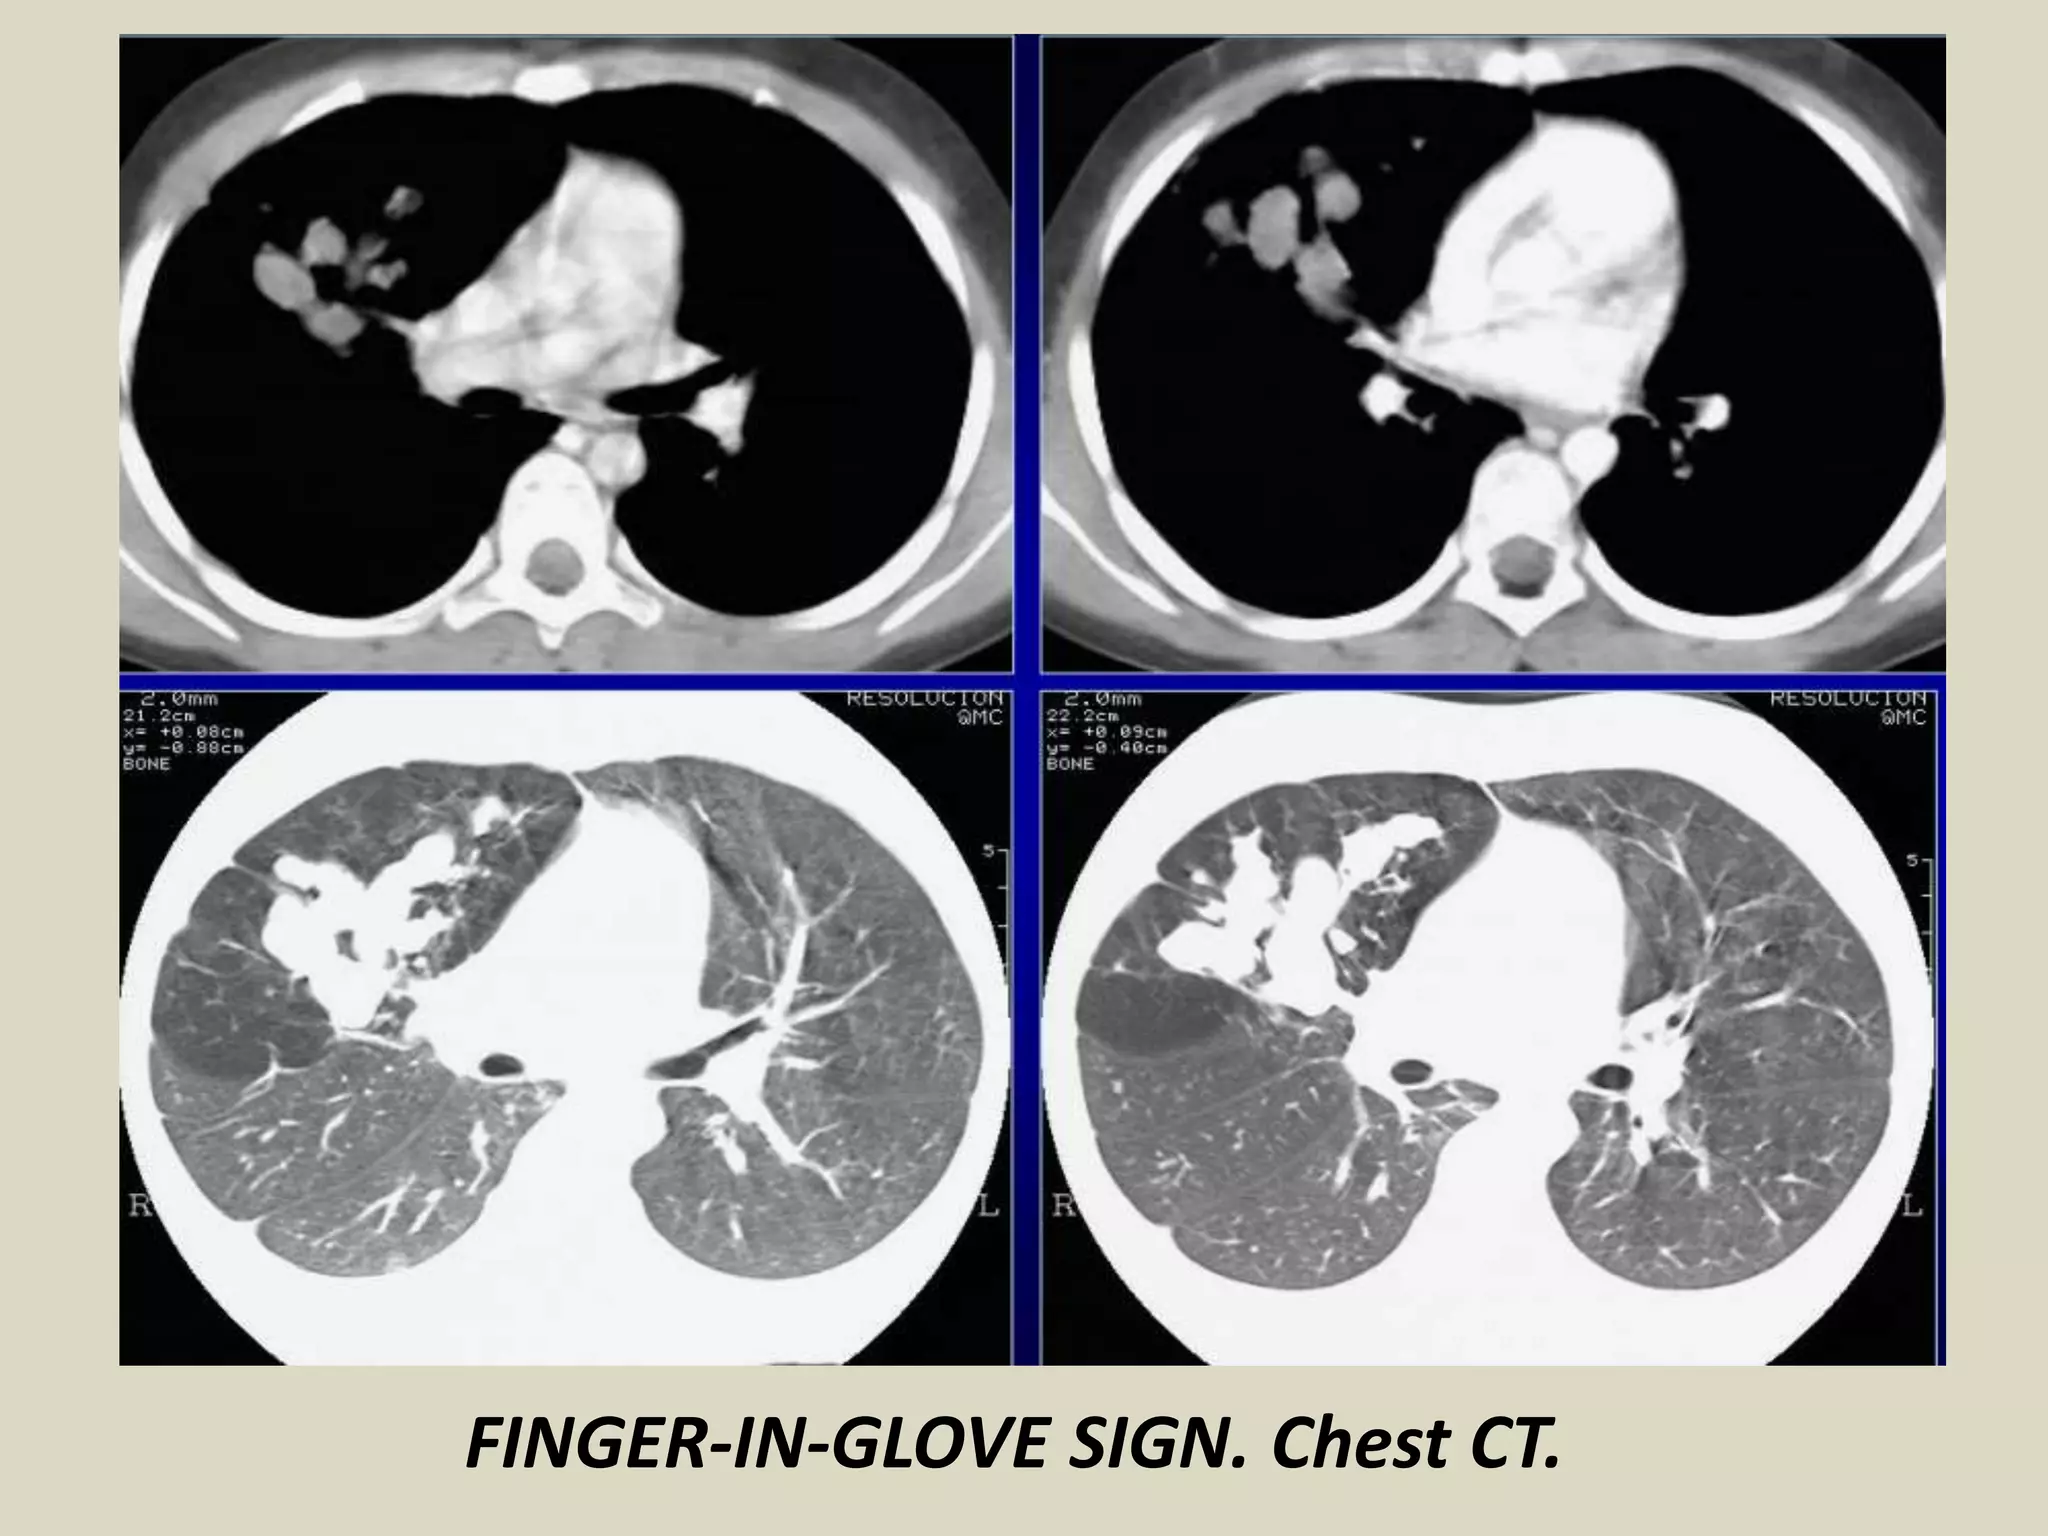

FINGER-IN-GLOVE SIGN

Visible on chest radiographs or CT

Indicates mucoid impaction within an obstructed bronchus

Characterized by branching tubular or fingerlike opacities

Originate from the hilum and are directed peripherally

Also seen in cases of dilated bronchi with secretions

Visualization of the gloved fingers is made possible by collateral air drift

through the interalveolar pores of Kohn and canals of Lambert aerating lung

distal to the point of mucoid impaction (distal lung remains aerated)

There are two broad etiologic categories: non-obstructive and obstructive

Non-obstructive:

- allergic bronchopulmonary aspergillosis (ABPA)

- asthma

- cystic fibrosis (secondary to mucociliary dysfunction and thick mucous

secretions)

Obstructive:

- neoplasms (bronchial hamartomas, lipomas, bronchogenic carcinoma,

carcinoid).

- congenital (bronchial atresia, intralobar sequestration, bronchogenic cysts).

FINGER-IN-GLOVE SIGN. Chest CT, schematic

drawing and illustrative picture.

FINGER-IN-GLOVE SIGN. Chest CT.